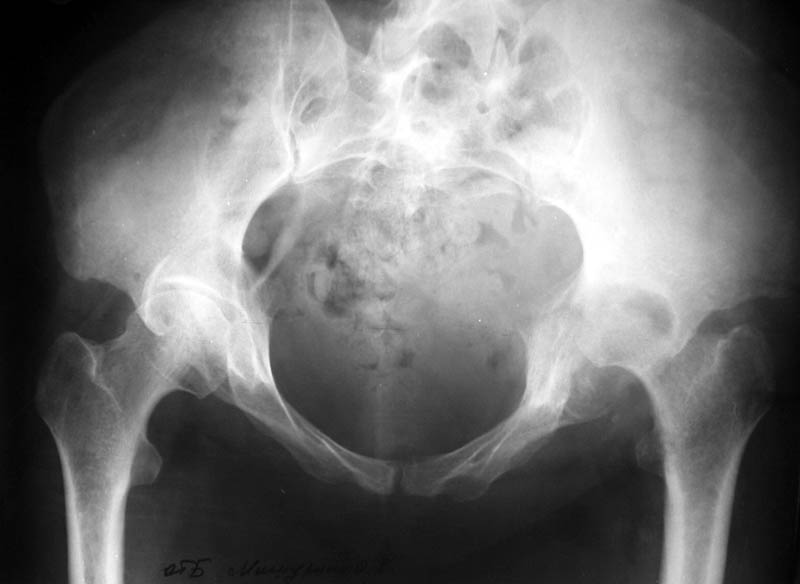

Женщина, 45 лет. В марте перенесла левосторонний коксит неизвестной этиологии. Специфику и онкологию исключили.

Интраартикулярных инъекций не было. Сейчас процесс клинически и рентгенологически - стабилизировался. Состояние вполне удовлетворительное. Предполагается тотальное эндопротезирование с пластикой полости аутокостью. Возможна ли бесцементная <чашка>? Заранее благодарю! С уважением, А.В.Владзимирский